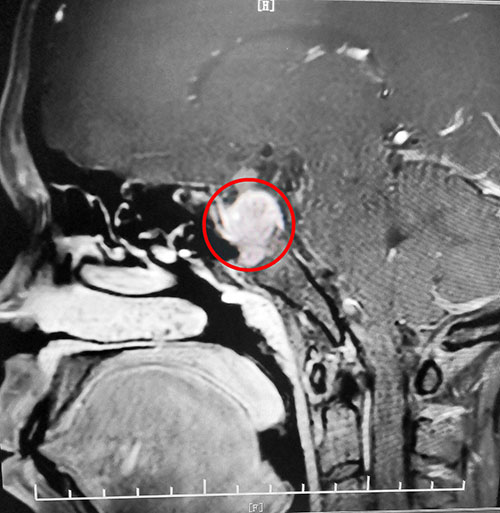

再查催乳素:1436μIU/mL。鞍区MRI平扫+增强显示,蝶鞍显著扩大,鞍区见不规则肿块影,大小约2.3*2.6*3.4cm。综合各项检查结合临床,刘女士被诊断为垂体大腺瘤(垂体瘤超过1厘米就是垂体大腺瘤)。

▲影像检查显示:垂体大腺瘤,超蝶鞍生长